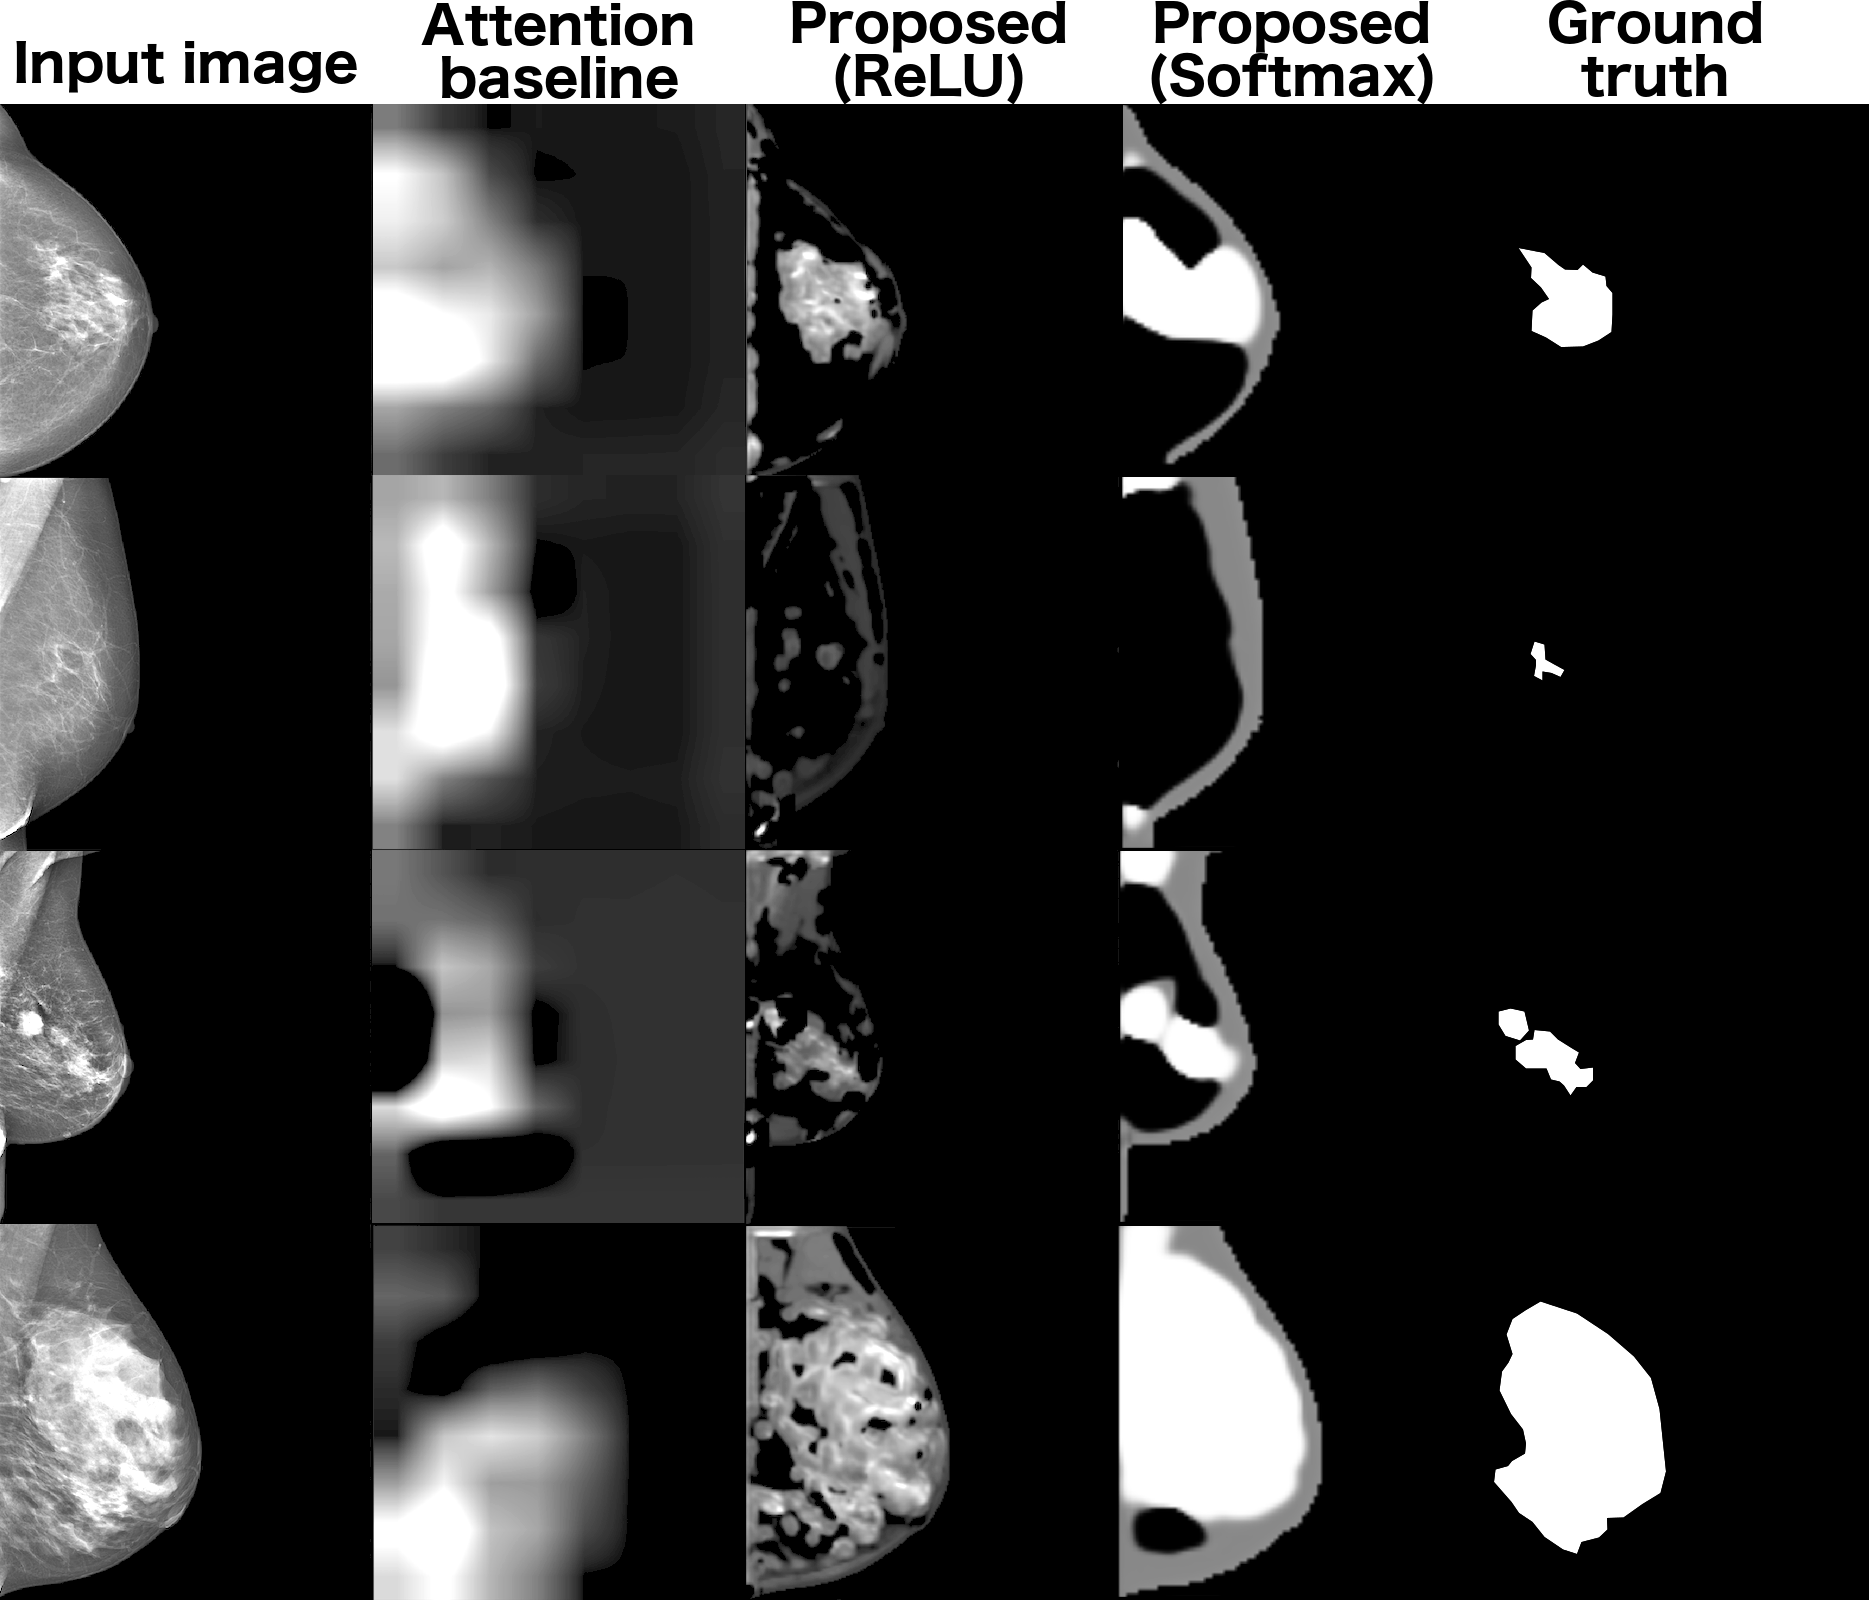

To validate the segmentation performance, we collected regions of interest on several images (16) and calculated the . Overall we obtain clinically meaningful segmentation masks offering valuable insights into the spatial distribution of the dense tissues (fig. LABEL:fig:dense_masks). In comparison, we demonstrate the inefficiency of the attention-based techniques for the breast density mask generation.